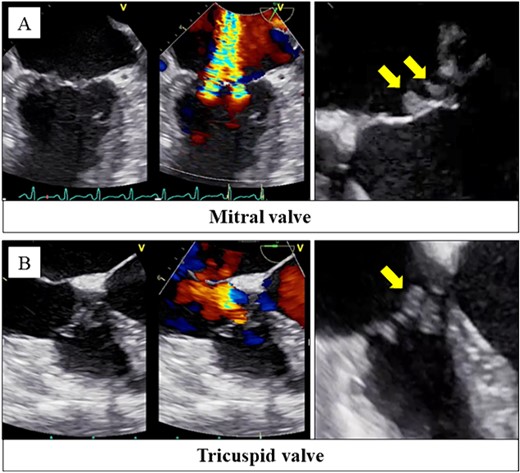

Her body temperature was 37.0°C. The laboratory test showed a white blood cell count of 7500 /μl, C-reactive protein of 1.07 mg/dl, platelet of 2.0 × 104 /μl, prothrombin time - international normalized ratio (PT-INR) of 3.47, fibrin degradation products of 66.9 μg/ml, and D-dimer of 21.4 μg/ml. Transthoracic echocardiography and transesophageal echocardiography revealed severe mitral and tricuspid regurgitation with mobile vegetations (Fig. 1A and B).

Transesophageal echocardiography revealed severe mitral regurgitation and tricuspid regurgitation with mobile vegetations on both valves (A, B).